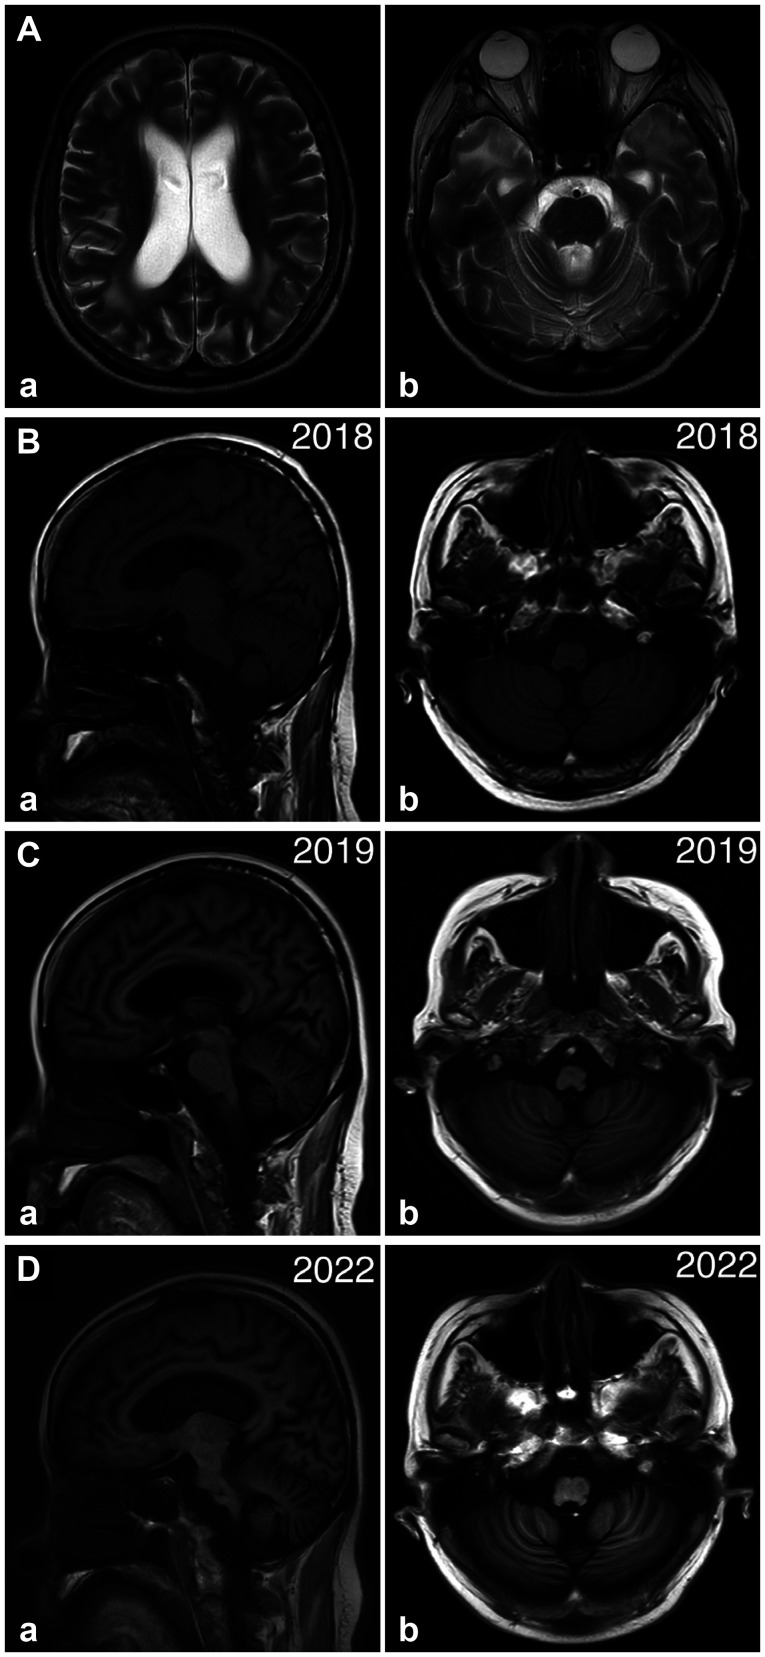

Myotonic Dystrophy Type 1 With Cerebellar Ataxia and Cerebellar Atrophy.

肌营养不良 1 型伴有小脑共济失调和小脑萎缩。